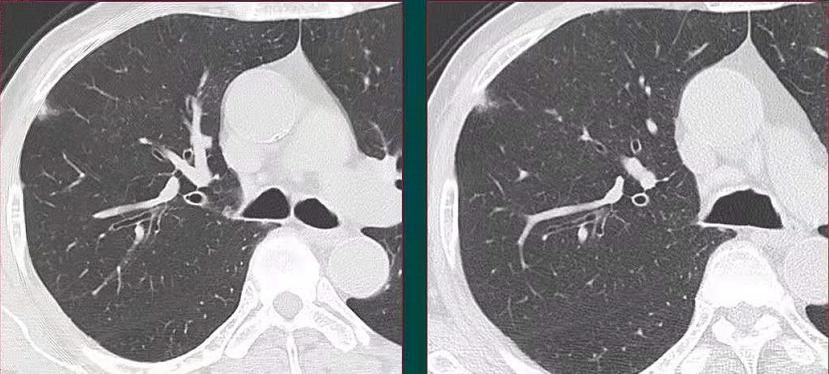

像这位60多岁的男性,没有症状,体检发现右肺斑片状影,边界不清,看起来很像一点炎症。

但他抗炎治疗后3-4个月复查显示,病灶没有消失,并且有缓慢增大的趋势:

狡猾的狐狸也藏不住自己的坏尾巴,果断手术切除,病理是浸润性粘液腺癌。